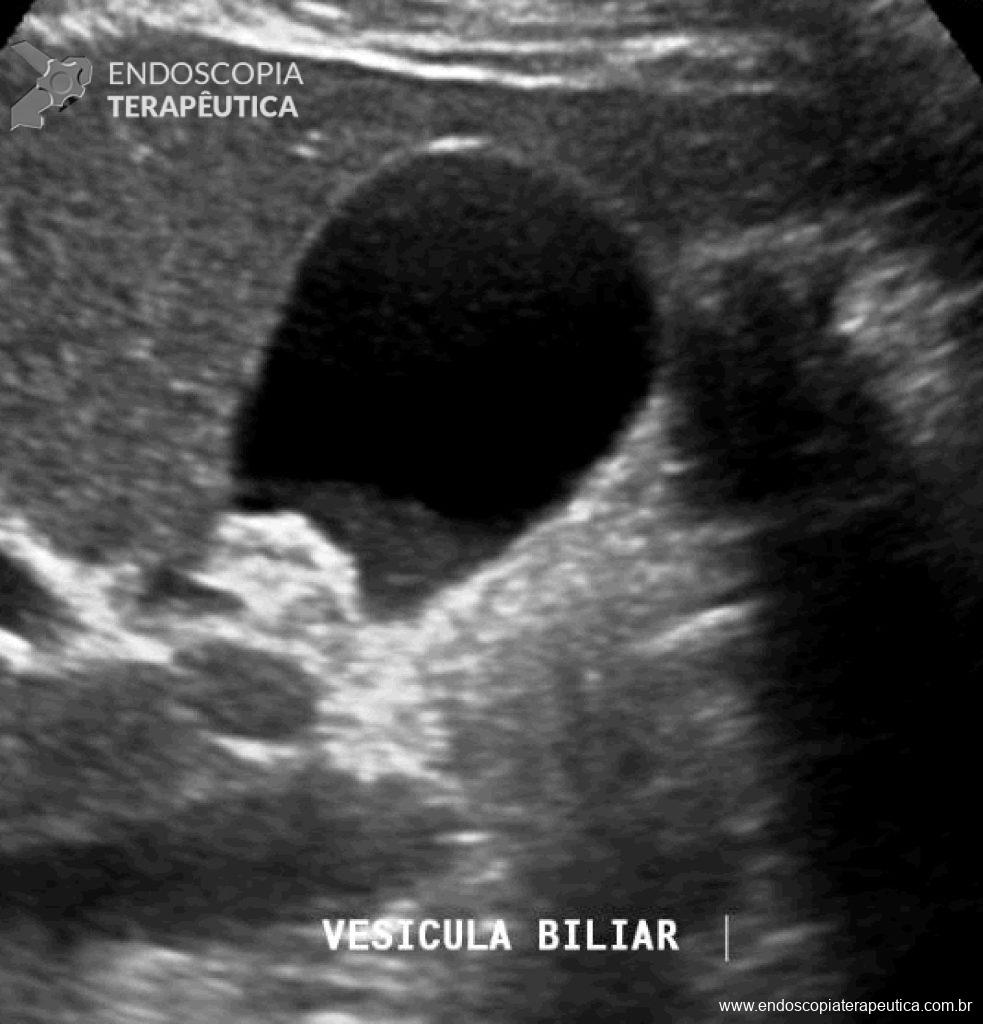

Descrito principalmente como um achado ultrassonográfico, a vesícula biliar apresenta um conteúdo hipoecogênico que se deposita formando nível em relação a bile mais fluída e sem formar sombra acústica posterior. O barro biliar muda de posição lentamente de acordo com o decúbito do paciente.